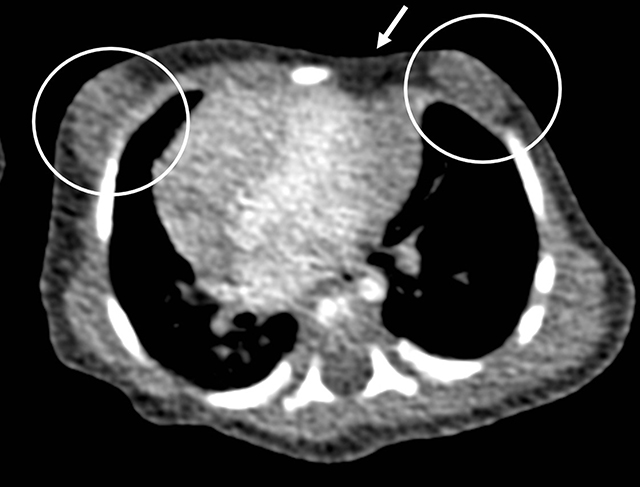

Figure 3

Axial CT-scan image in mediastinal window shows absence of the sternocostal head of the left major pectoral muscle (white arrow) with subsequent depression in the left chest wall. There is bilateral gynaecomastia (circles). The heart is positioned more to the right side than normal.